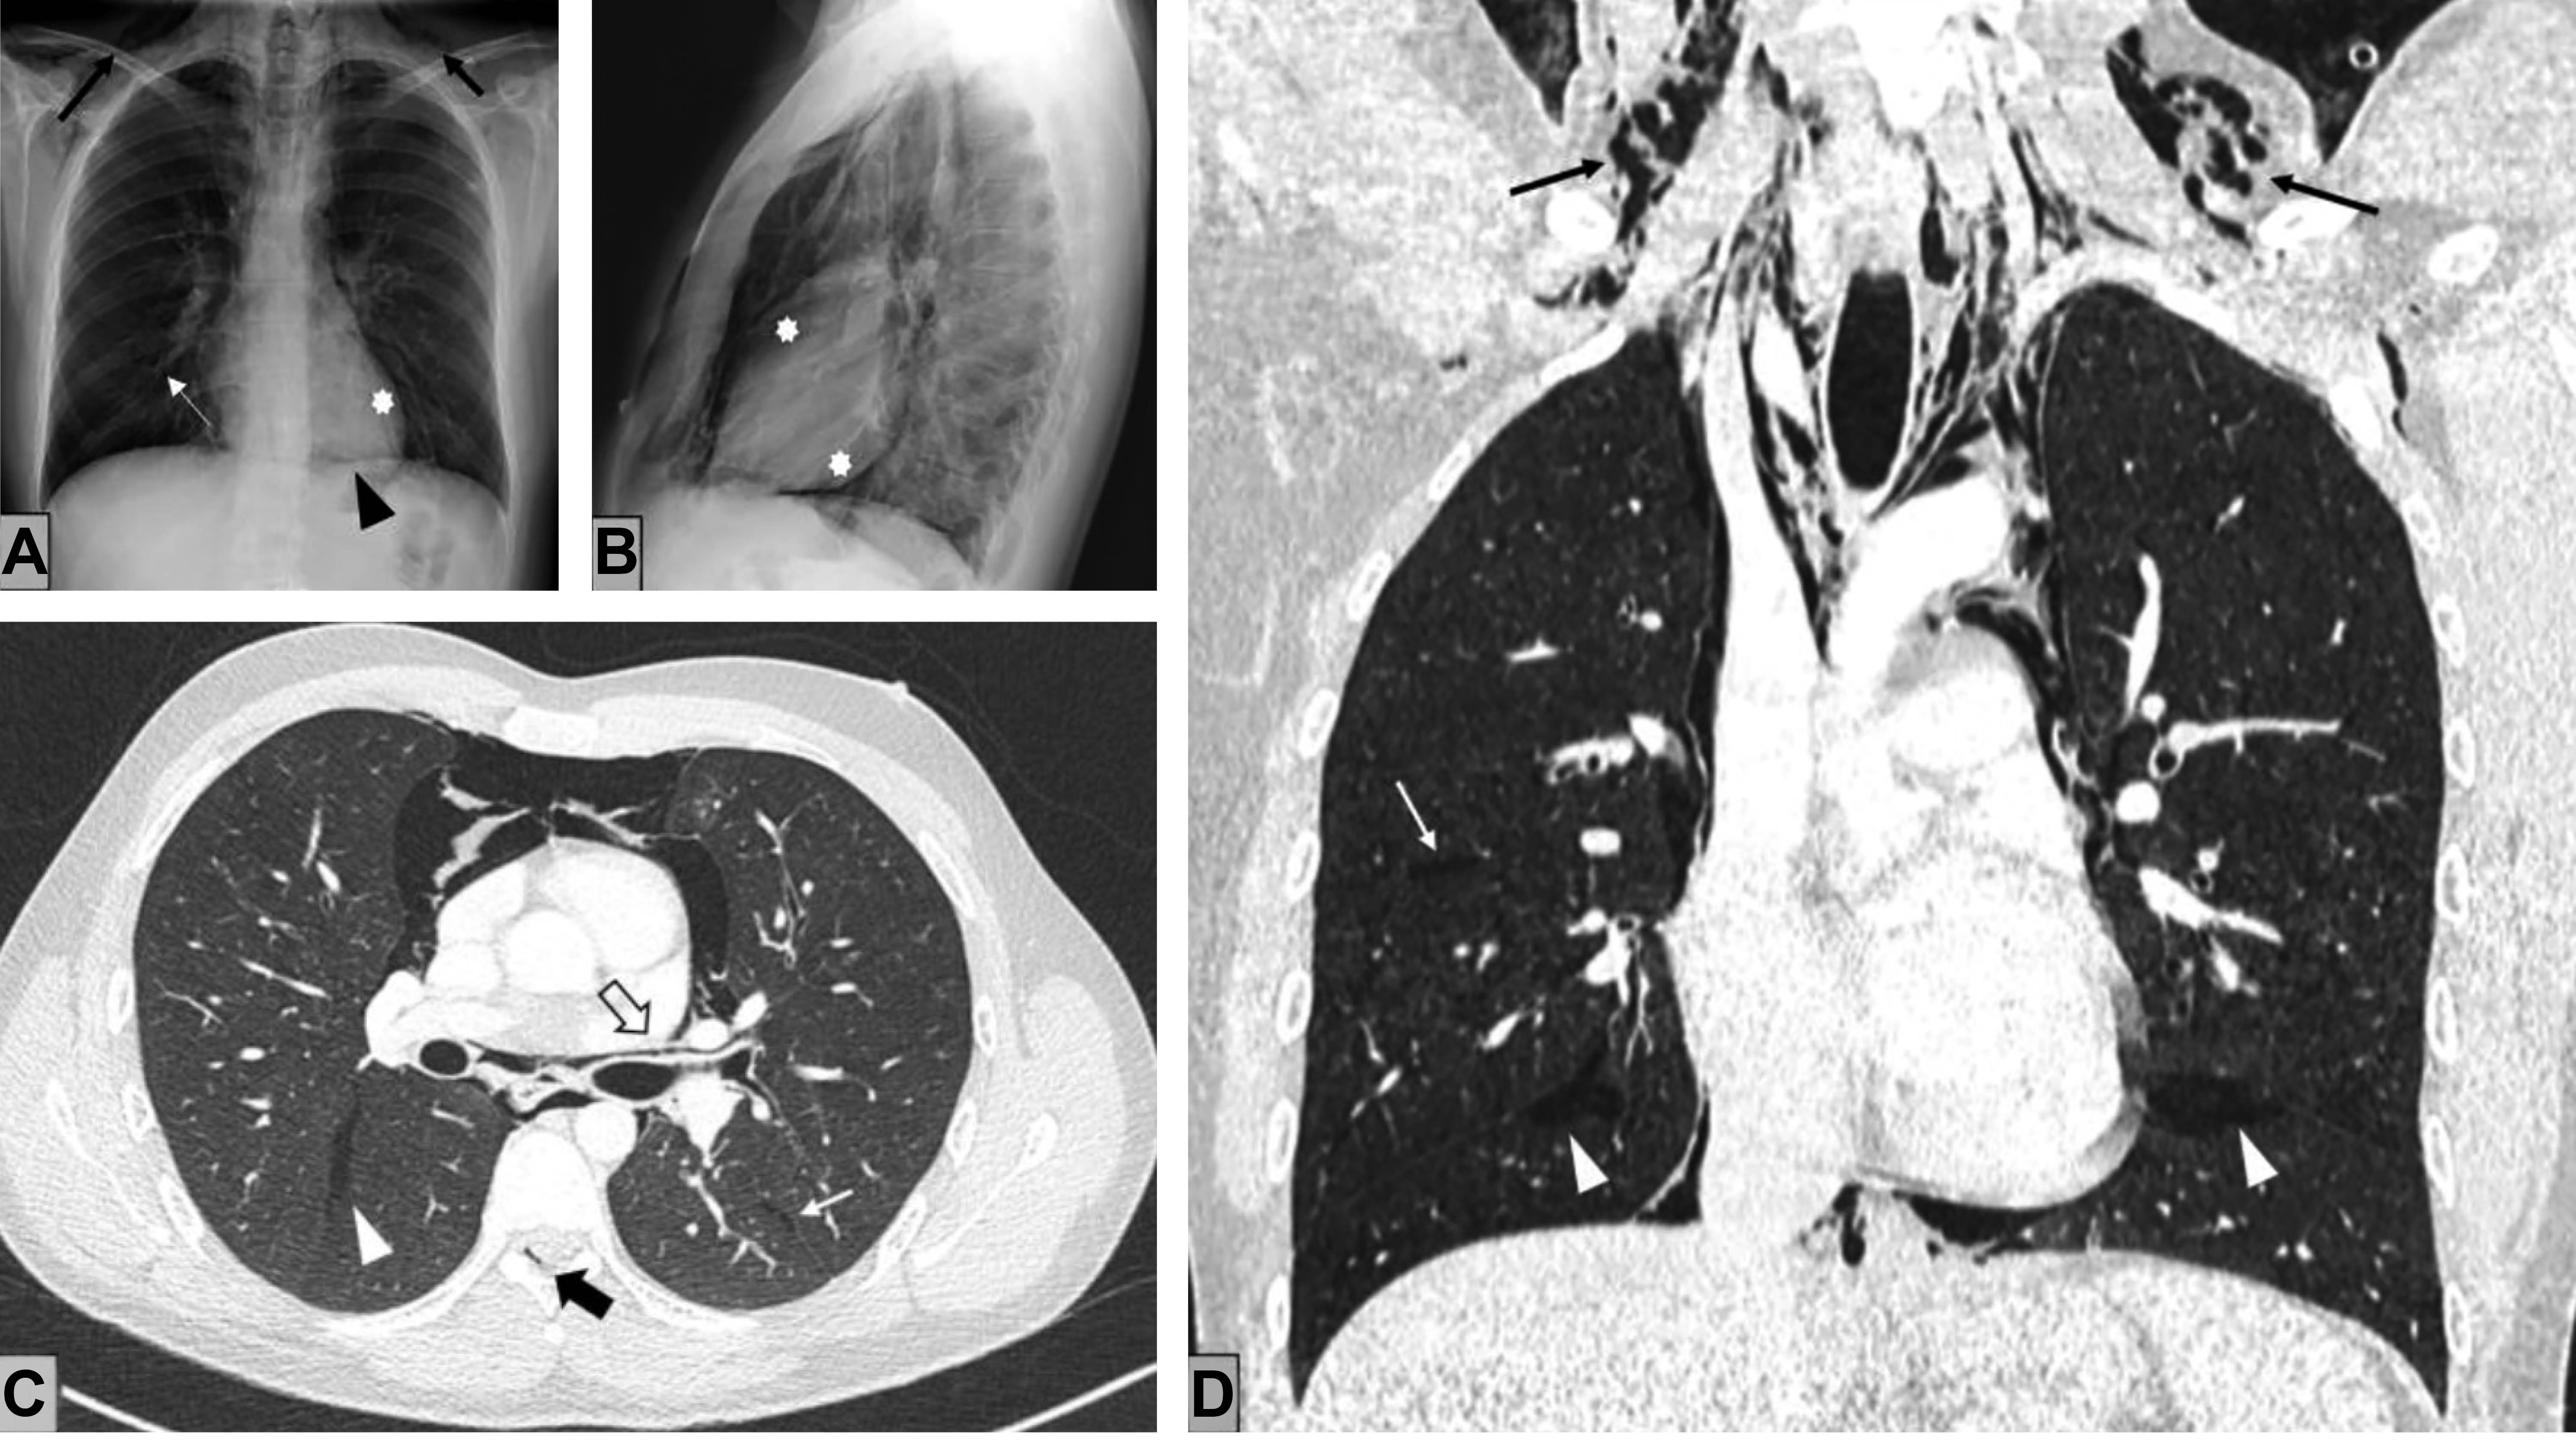

Se realiza una radiografía de tórax y se identifican signos de neumomediastino y enfisema subcutáneo cervical bilateral (Figura 1A y B). Se completa el estudio con una tomografía computarizada (TC) torácica, lo que confirma la presencia de neumomediastino con extensión a los planos cervicales profundos disecando los compartimentos mediastínicos (Figura 1C y D).

El aire ectópico se extiende desde el intersticio pulmonar hasta la región hiliar, lo que conforma múltiples colecciones en áreas peribronquiales de morfología lineal (efecto Macklin). También se identifica contenido aéreo en cisuras pleurales y en espacio epidural (neumorraquis).

La primera prueba radiológica realizada suele ser la radiografía de tórax, la cual evidencia enfisema subcutáneo y neumomediastino. En la TC, la rotura alveolar no suele resultar perceptible, pudiéndose objetivar colecciones aéreas lineales en torno a las vainas broncovasculares (efecto Macklin).

En el contexto clínico compatible, y excluyendo los casos asociados a traumatismo torácico grave o a síntomas compatibles con síndrome de Boerhaave, el efecto Macklin se considera altamente sugestivo de neumomediastino espontáneo de origen respiratorio, por lo que resulta clave en la orientación etiológica del cuadro y en el diagnóstico diferencial con las formas de neumomediastino secundario.4